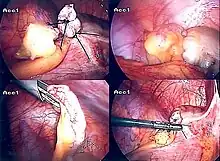

The surgical procedure for the removal of the appendix is called an appendectomy. Appendectomy can be performed through open or laparoscopic surgery. Laparoscopic appendectomy has several advantages over open appendectomy as an intervention for acute appendicitis.[76]

Laparoscopic appendectomy

Laparoscopic appendectomy was introduced in 1983 and has become an increasingly prevalent intervention for acute appendicitis.[80] This surgical procedure consists of making three to four incisions in the abdomen, each 0.25 to 0.5 inches (6.4 to 12.7 mm) long. This type of appendectomy is made by inserting a special surgical tool called a laparoscope into one of the incisions. The laparoscope is connected to a monitor outside the person's body, and it is designed to help the surgeon to inspect the infected area in the abdomen. The other two incisions are made for the specific removal of the appendix by using surgical instruments. Laparoscopic surgery requires general anesthesia, and it can last up to two hours. Laparoscopic appendectomy has several advantages over open appendectomy, including a shorter post-operative recovery, less post-operative pain, and lower superficial surgical site infection rate. However, the occurrence of an intra-abdominal abscess is almost three times more prevalent in laparoscopic appendectomy than open appendectomy.[81]